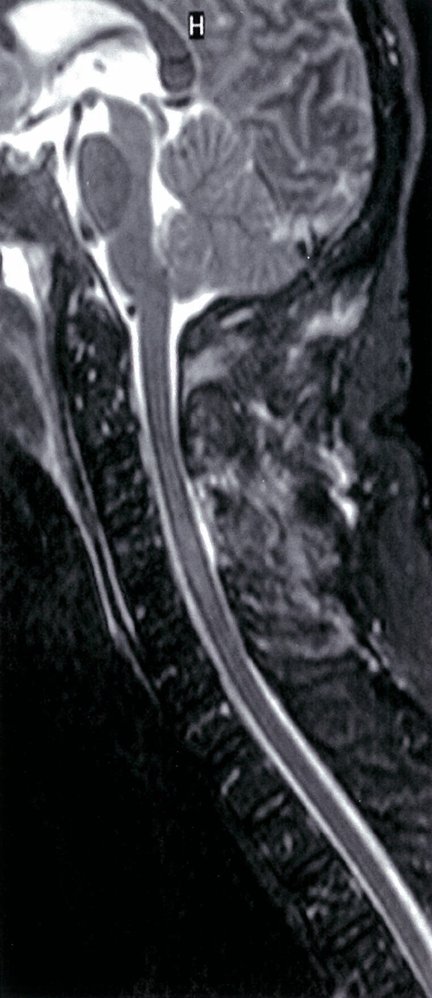

• MRI of the spine (imaging modality of choice) : determines the site of narrowing of the medulla and the underlying pathology

• Myelography (possibly with CT): if MRI is contraindicated (e.g., in patients with metal implants)